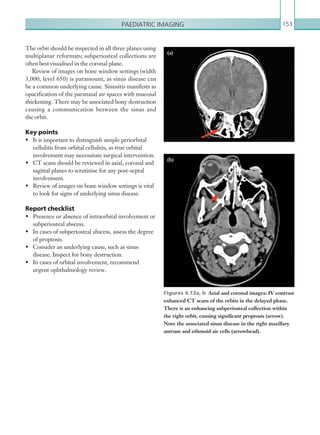

• 61.

Gastrointestinal and genitourinaryimaging 39 Figure 2.20  Axial image: IV contrast enhanced CT scan of the abdomen in the portal venous phase. There is a wedge-shaped low attenuation within the spleen in keeping with an infarct. Figure 2.21  Axial image: IV contrast enhanced CT scan of the abdomen in the portal venous phase. ­Multiple locules of gas can be seen within the wall of the bowel, secondary to bowel ischaemia. Figure 2.22  Axial images: IV contrast enhanced CT scan of the abdomen in the portal venous phase. Large volumes of portal venous gas are seen within the liver extending to the periphery. Figure 2.23  Axial image: IV contrast enhanced CT scan of the abdomen in the portal venous phase. The mesenteric vessels are engorged and the mesenteric fat has a hazy appearance. K22247_C002.indd 39 16/05/15 3:07 AM

• 62.

Chapter 240 backwash ileitis).Infective enterocolitis can affect any part of the bowel (Table 2.7). Pseudomembranous colitis commonly affects the descending and transverse colon and typically causes much more pronounced wall thickening (10–15 mm) than other causes (Figure 2.24). Neutropaenic enterocolitis typically involves the terminal ileum, caecum and ascending colon, although ahistoryofchemotherapyandneutropaeniaisthemost helpful tool to make this diagnosis. Utilisation of lung and bone window settings is also useful to identify free intra-abdominal gas, suggestive of associated bowel perforation. Toxic megacolon is a complication of most colitides and is a risk factor for imminent perforation. This is diagnosed when there is colonic dilatation (transverse colon 6 cm) in the presence of associated colonic inflammation. Any suspicion of toxic megacolon should be urgently discussed with the referring team. Plain films The hallmark of enterocolitis on plain radiographs is bowel wall thickening, although again this is a difficult diagnosis to make due to variable bowel collapse (Figure 2.25). A ‘thumbprinting’ pattern can be observed in the colon, representing thickened haustral folds, although this has a wide differential. CAUSATIVE ORGANISM DISTRIBUTION Clostridium difficile (pseudomembranous colitis) Descending and transverse colon. Salmonella spp. Colonic inflammation only. Campylobacter spp. Typically in distal colon. Yersinia spp. Typically terminal ileum and caecum. Mycobacterium spp. Typically terminal ileum and caecum. Entamoeba histolytica Diffuse colonic involvement, typically ascending colon. Shigella spp. Typically rectosigmoid colon. Table 2.7 Typical distribution of infective colitides. Figure 2.24  Axial image: IV contrast enhanced CT scan of the abdomen in the portal venous phase. There is marked bowel wall thickening ­involving the ­descending colon (arrow), typically seen in ­pseudomembranous colitis. Figure 2.25  Supine abdominal radiograph. There is thickening of the bowel wall involving the descending colon (arrow), consistent with colitis. No intraperitoneal free gas is seen. K22247_C002.indd 40 16/05/15 3:07 AM

• 63.

Gastrointestinal and genitourinaryimaging 41 LARGE BOWEL OBSTRUCTION Large bowel obstruction (LBO) is a common surgical emergency that can occur as a result of many varying pathologies. One of the commonest causes of LBO in western countries is malignancy, usually as a result of primary large bowel carcinoma (Khurana et al., 2002). Invasive malignancies may infiltrate the mucosa, eventually occluding the lumen and resulting in obstruction. Chronic diverticulitis and radiotherapy to the pelvis may lead to fibrosis and stricturing of the bowel. Large bowel volvulus is another common cause of obstruction; this occurs when there is twisting of the mesentery resulting in a closed loop obstruction. This leads to bowel obstruction; however, the closed loop of bowel is also at risk of ischaemia. Causes of LBO include: • Colonic malignancy. • Inflammatory strictures: Crohn’s, ischaemia, diverticulitis. • Volvulus. • Infective processes: TB, amoebiasis. • Extrinsic lesions: abscess, bladder/prostate/uterine tumour, endometriosis. Clinically, patients may present with abdominal pain, distension and vomiting. They may also report an inability to pass stool or flatus. If complicated by perforation, patients may demonstrate peritonism and haemodynamic instability (see Bowel perforation). Urgent imaging is often necessary to help plan surgery.ThemanagementofLBOvariesdependingon the underlying aetiology. Most cases typically require surgical resection for relief of symptoms, although lesions that cannot be completely resected may instead undergo bowel defunctioning and creation of a stoma. In palliative cases, colonic stents may be inserted in Key points • Enterocolitis may be ischaemic, inflammatory or infective in nature. • Acute bowel ischaemia is a surgical emergency and has a high mortality rate. Prompt diagnosis is essential in order to facilitate urgent surgical treatment. • CT is the modality of choice to investigate cases of bowel ischaemia; however, imaging should not delay emergency laparotomy in strongly suspected cases. • There is significant overlap in the radiological findings of enterocolitis; however, absent or diminished bowel wall enhancement corresponding to an arterial territory is highly suggestive of ischaemia. Report checklist • Presence or absence of free gas, indicative of perforation. • Presence or absence of gas within the bowel wall or the portal venous system. • Presence or absence of filling defects in the coeliac axis/SMA/IMA/SMV or any of their branches. • Consider embolic disease in cases of visceral infarcts. The presence or absence of potential embolic sources (e.g. thrombus in the left atrial appendage/left ventricular aneurysm/infarct/aortic dissection/aortic aneurysm). • Consider a differential diagnosis of additional causes of enterocolitis. Reference Sung ER, Hyun KH, Soo-Hyun L et al. (2000) CT and MR imaging findings of bowel ischemia from various primary causes. RadioGraphics 20:29–42. K22247_C002.indd 41 16/05/15 3:07 AM

• 64.

Chapter 242 Radiological findings Plainfilms On an abdominal plain film, the diagnosis of LBO is made by identifying dilated large bowel loops. In a normal patient, the caecum should not measure more than 8–9 cm and the remainder of the large bowel should not measure more than 5 cm, therefore a bowel diameter greater than these values may suggest underlying LBO (Figure 2.26). The distribution of bowel dilatation is key; in LBO, large bowel collapse distal to the point of obstruction would be expected. Dilated loops of small bowel may also be present, indicating ileocaecal valve incompetence. In cases where a nasogastric (NG) tube has been placed, the tip should be located under the left hemidiaphragm. order to relieve symptoms. Sigmoid volvulus is initially managed conservatively with a rectal flatus tube insertion, but persisting volvuli may require surgical decompression. Radiological investigations An abdominal and erect chest plain film is indicated in patients who present with signs of LBO. An abdominal plain film may confirm the presence of obstruction; however, the underlying cause is unlikely to be apparent. Definitive diagnosis is routinely made with contrast enhanced CT imaging. It is not usually necessary to administer oral contrast, as the level of obstruction is usually identifiable as an abrupt calibre change or mass. Furthermore, patients who are acutely obstructed are unlikely to be able to ingest the volume of oral contrast required to adequately opacify the bowel. It is important to note that large bowel volvulae normally have a typical appearance on plain films and, as a result, CT imaging is not routinely required to make this diagnosis. The use of water soluble single contrast enema has largely been replaced with CT, though some centres may still practise this. Contrast administered rectally flows proximally through the large bowel and does not pass beyond the point of obstruction. If the procedure is performed, water soluble contrast should be used due to the risk of bowel perforation and hence leakage into the peritoneum. (See Table 2.8.) MODALITY PROTOCOL CT IV contrast, portal venous phase: 100 ml IV contrast, 4 ml/sec via 18G cannula. Scan at 70 seconds. Scan from just above the ­diaphragm to just below the pubic symphysis. Plain film imaging Erect CXR to include the diaphragm. ­Abdominal plain film imaging to include the liver to the pubic symphysis. Table 2.8 Large bowel obstruction. Imaging protocol. Figure 2.26  AP radiograph of the abdomen. Dilated loops of large bowel are seen in the right abdomen, ­indicated by the lack of valvulae conniventes. The ­ileocaecal valve is patent, resulting in reflux of gas into small bowel loops seen centrally and in the left abdomen. K22247_C002.indd 42 16/05/15 3:07 AM

• 65.

Gastrointestinal and genitourinaryimaging 43 LBO secondary to malignancy or stricture formation may have similar radiological findings; however, volvulae tend to have a slightly different appearance, which can often allow them to be diagnosed on plain film images. Sigmoid volvulus is the commonest type of volvulus, and occurs when the colon twists about its mesentery. It tends to occur in slightly older patients compared with those who have a caecal volvulus. The classic findings include the presence of a ‘coffee bean’ appearance to the dilated loop, an inverted ‘U’ shape and the loop extending into the upper abdomen from the pelvis (Figure 2.27). The sigmoid colon is also usually ahaustral in comparison with caecal volvulus, which normally retains its normal haustral pattern. The other main feature of caecal volvulus is extension of the dilated loop of bowel from the right lower quadrant to the left upper quadrant. The differences between sigmoid and caecal volvulae are summarised in Table 2.9. SIGMOID CAECAL Typical plain film findings Coffee bean sign. Large bowel dilatation proximally. Ahaustral closed loop. Inferior convergence in the LIF. Left flank overlap sign. Dilated caecum may be seen in the mid abdo- men or LUQ. Haustrations usually present. Associated small bowel dilatation. LIF = left iliac fossa; LUQ = left upper quadrant. Table 2.9  Sigmoid vs. caecal volvulus. Computed tomography IV contrast enhanced CT is used not only to diagnose the presence of LBO, but also the underlying cause, allowing evaluation of luminal and extraluminal bowel structures. Initial review of the CT should begin by confirming the presence of LBO, indicated by large bowel dilatation proximal to an abrupt transition point. The same numerical values should be used as for plain film imaging (see above). Dilated large bowel loops should be traced distally in order to identify a mechanical cause of the obstruction. This can usually be seen as a transition in the calibre of the bowel from dilated to normal, or often collapsed beyond the point of obstruction. A quick review on lung window settings (width 1,500, level 500) is helpful to reveal any evidence of free intra-abdominal gas, suggestive of bowel perforation. If this is seen, the surgical team should be informed as a matter of urgency as the patient may require emergency surgery. Figure 2.27  AP radiograph of the abdomen. There are dilated loops of large bowel, which arise from the pelvis with an inverted ‘U’ appearance suggestive of sigmoid volvulus. K22247_C002.indd 43 16/05/15 3:07 AM

• 66.

Chapter 244 Large bowelvolvulus has a distinctive appearance on CT imaging. Proximal loops of dilated large bowel are visible, as seen with other causes of obstruction; however, the transition point is seen as a tapering of the bowel lumen to a point of completely collapsed bowel. It is vitally important to scrutinise the extraluminal appearance in these cases. The underlying cause of volvulus (both caecal and sigmoid) is a twisting of the mesentery. On CT, this can be seen as a ‘swirling’ of vessels that appear to rotate about the axis of torsion (Figure 2.30) at the site of the involved loop of bowel. The axis of twisting may not be easily seen on axial imaging, and coronal and sagittal reformats should therefore be used to confirm the diagnosis. Incaseswherethereislargeboweldilatationwithout a mechanical cause of obstruction, colonic pseudo- obstruction may be present. Pseudo-obstruction is diagnosed when there are symptoms of bowel obstruction and there is large bowel dilatation on imaging, but no identifiable mechanical obstruction. Often there is a gradual tapering of the bowel rather than an immediate point of transition. Alternatively, In cases of malignant obstruction, a soft tissue mass can often be seen occluding the lumen (Figure 2.28). Subtle tumours can be easy to miss, manifesting as concentric or eccentric mural thickening. Advanced tumours may also demonstrate extension through the serosa, adjacent lymphadenopathy or distant metastases (usually to the liver, appearing as ill-defined flow attenuation lesions). Obstruction secondary to stricture formation may be seen as a narrowed segment of bowel at the point of calibre transition (Figure 2.29). This can be a difficult diagnosis to make on a single study since physiologically collapsed bowel can have a similar appearance; correlation with previous imaging is useful in this regard. In general, malignancies tend to be shorter segment areas of mural thickening, whereas strictures tend to be longer segments of collapsed bowel; however, it can often be difficult to exclude the presence of a small malignant obstructing lesion within a stricture (particularly in the absence of adequate bowel preparation). Colonoscopy is therefore often needed and should be recommended in order to assess the abnormal segments of bowel in further detail. Figure 2.28  Axial image: IV contrast enhanced CT scan of the abdomen and pelvis in the portal venous phase. A solid mass lesion is seen within the mid-­ sigmoid colon (arrow), occluding the lumen and ­resulting in upstream dilatation of the bowel. Figure 2.29  Axial image: IV contrast enhanced CT scan of the abdomen in the portal venous phase. There is a long stricture of the mid-sigmoid colon with a ­massively dilated loop of proximal sigmoid colon shown. A single diverticulum is shown in this image. The ­stricture was due to chronic diverticulitis. K22247_C002.indd 44 16/05/15 3:07 AM

• 67.

Gastrointestinal and genitourinaryimaging 45 Report checklist • Degree and level of bowel obstruction. • Presence or absence of complications such as perforation or bowel ischaemia. • Consider underlying causes such as malignancy or post-inflammatory strictures. • Document the degree of local or distant disease in cases of malignancy; this determines whether the patient has palliative as opposed to curative surgical treatment. References Choi JS, Lim JS, Kim H et al. (2008) Colonic pseudoobstruction: CT findings. Am J Roentgenol 190:1521–1526. KhuranaB,LedbetterS,McTavishJ et al.(2002)Bowel obstruction revealed by multidetector CT. Am J Roentgenol 178:1139–1144. multiple segments of colonic dilatation and collapse are seen, the distribution of which is not suggestive of mechanical obstruction. Patients with pseudo- obstruction tend to suffer with constipation, with a suggested underlying cause thought to be related to the intrinsic nerve supply of the bowel (Choi et al., 2008). Key points • Large bowel obstruction is a surgical emergency which, if left untreated, may result in bowel perforation or ischaemia. • CT imaging can confirm the diagnosis and identify the underlying cause, although the presence of LBO may be confirmed on plain film images. • LBO is suggested on CT imaging by large bowel dilatation (caecum 8–9 cm, remainder of large bowel 5 cm) proximal to a focal transition point, usually with large bowel collapse distally. Figure 2.30  Coronal image: IV contrast enhanced CT scan of the abdomen and pelvis in the portal venous phase. A loop of sigmoid colon can be seen in the midline, which comes to an abrupt stop (arrow). The adjacent vessels demonstrate a swirling appearance, ­suggestive of twisting of the mesentery. K22247_C002.indd 45 16/05/15 3:07 AM

• 68.

Chapter 246 GALLSTONE ILEUS Gallstoneileus is an uncommon cause of mechanical small bowel obstruction (SBO). It is a complication of chroniccholecystitisandoccurswhenagallstonepasses through a cholecystenteric fistula located between the gallbladder and the duodenum. The gallstone impacts within the small bowel, resulting in SBO. Overall, gallstone ileus is an uncommon cause of SBO (4%), but in the elderly population it is more common, accounting for up to 25% of non- strangulated bowel obstructions and resulting in significant morbidity in this group (Lassandro et al., 2005). Pathologically, gallstone ileus results from repeated boutsofcholecystitisresultinginadhesionsbetweenthe gallbladder and the small bowel (usually duodenum), eventually leading to fistula formation and passage of gallstones into the lumen of the bowel. Patients usually present with a long history of recurrent right upper quadrant pain, in keeping with chronic cholecystitis. The acute presentation of gallstone ileus is that of a small bowel obstruction, with colicky abdominal pain and abdominal distension. Radiological investigations A plain abdominal radiograph is useful as a first-line investigationinpatientswithsuspectedSBO.Suspicion of gallstone ileus on plain film imaging necessitates CT imaging of the abdomen, which has a sensitivity, specificity and accuracy of diagnosing gallstone ileus of 93%, 100% and 99%, respectively (Yu et al., 2005). Ultrasound is useful in assessment of patients with right upper quadrant pain to identify the presence of gallstones or cholecystitis. (See Table 2.10.) Radiological findings Plain films The classic findings on an abdominal radiograph are of SBO (dilated loops of small bowel 2.5 cm), gas within the biliary tree (linear branching lucencies projected over the right upper quadrant) and a gallstone (usually in the right iliac fossa) (Figure 2.31). This is known as Rigler’s triad. MODALITY PROTOCOL CT IV contrast, portal venous phase: 100 ml IV contrast, 4 ml/sec via 18G cannula. Scan at 70 seconds. Scan from just above the diaphragm to just below the pubic symphysis. Plain film imaging Abdominal plain film imaging to ­include the liver to the pubic ­symphysis. Ultrasound 1–5MHz curvilinear probe. Table 2.10  Galltone ileus. Imaging protocol. Figure 2.31  AP abdominal radiograph. Multiple loops of dilated small bowel can be seen, consistent with SBO. Linear, branching lucencies can be seen at the right upper quadrant consistent with biliary gas (arrow). The ­findings are consistent with gallstone ileus. No ­radiopaque ­gallstone can be seen on the radiograph. K22247_C002.indd 46 16/05/15 3:07 AM